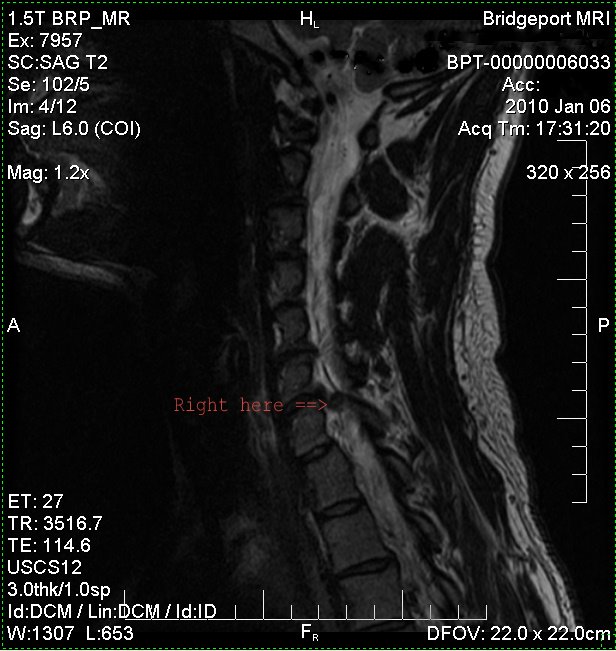

| The Badly Herniated Disk between C-6 and C-7. |

The North Lake Group, lead by Physical Therapist and North Lake founder Cheryl Kosta, took me under their healing wing back in February 2010 - after my C6/7 artificial disk replacement surgery. This surgery corrected my badly herniated disk which resulted in excruciating pain, muscle waisting on my left shoulder, pectoral, bicep and triceps, numbness in my left hand and paralysis in my left triceps.